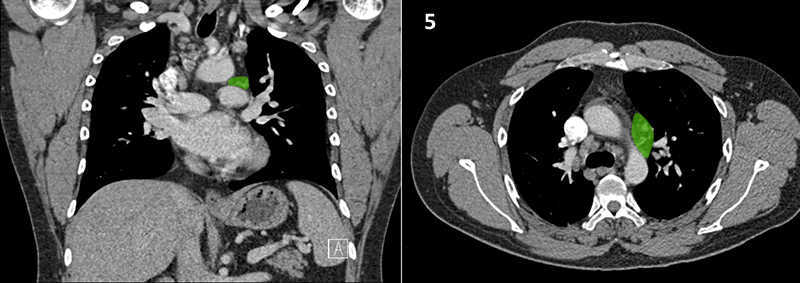

Nodal zones and stations according to the International Association for the Study of Lung Cancer (IASLC) node map.

Table (above): Nodal zones and stations according to the International Association for the Study of Lung Cancer (IASLC) node map. (Source: 1,2) *Depends on the side of the tumour.